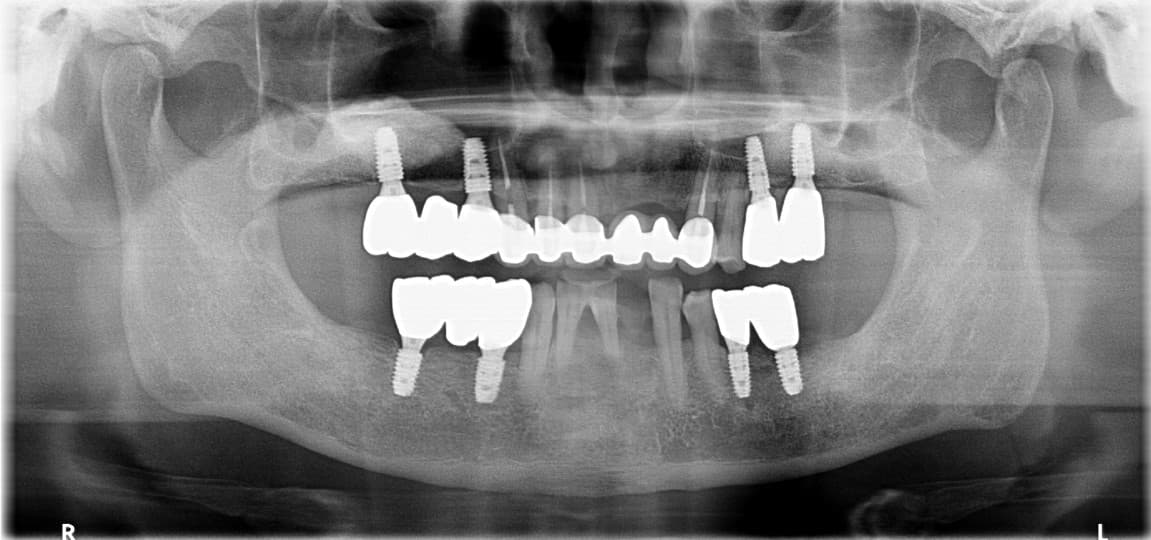

Tối thiểu số lượng Implant, Tối thiểu xâm lấn,

Tối thiểu ghép xương

Chẩn đoán kỹ thuật số chính xác đảm bảo chỉ thực hiện các thủ thuật cần thiết tối thiểu.

Tối thiểu số lượng Implant

Chỉ 6 trụ hàm trên và 4 trụ hàm dưới để cố định chắc chắn

Tối thiểu xâm lấn

Hồi phục nhanh chóng với phẫu thuật xâm lấn tối thiểu

Chẩn đoán chính xác để giảm thiểu việc ghép xương